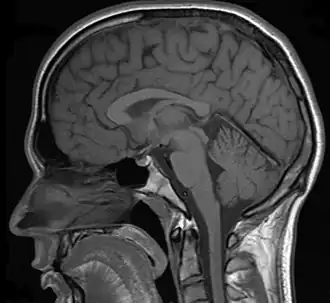

Neuroimaging can be a valuable tool in the diagnostic work-up of various psychiatric disorders including depression.[1]

In a case of misdiagnosed depression recounted in Newsweek, a writer received treatment for depression for years; during the last 10 years of her depression the symptoms worsened, resulting in multiple suicide attempts and psychiatric hospitalizations. When an MRI finally was performed, it showed the presence of a tumor. However, she was told by a neurologist that it was benign. After a worsening of symptoms, and upon the second opinion of another neurologist, the tumor was removed. After the surgery, she no longer had depressive symptoms.[28]

MRI brain scan: Neurocysticercosis

• Neurocysticercosis (NCC): is an infection of the brain or spinal cord caused by the larval stage of the pork tapeworm, Taenia solium. NCC is the most common helminthic (parasitic worm) infestation of the central nervous system worldwide. Humans develop cysticercosis when they ingest eggs of the pork tapeworm via contact with contaminated fecal matter or eating infected vegetables or undercooked pork.[37] "While cysticercosis is endemic in Latin America, it is an emerging disease with increased prevalence in the United States."[38] "The rate of depression in those with neurocysticercosis is higher than in the general population."[39]

In addition to pituitary tumors, tumors in various locations in the central nervous system may cause depressive symptoms and be misdiagnosed as depression.[28][69]